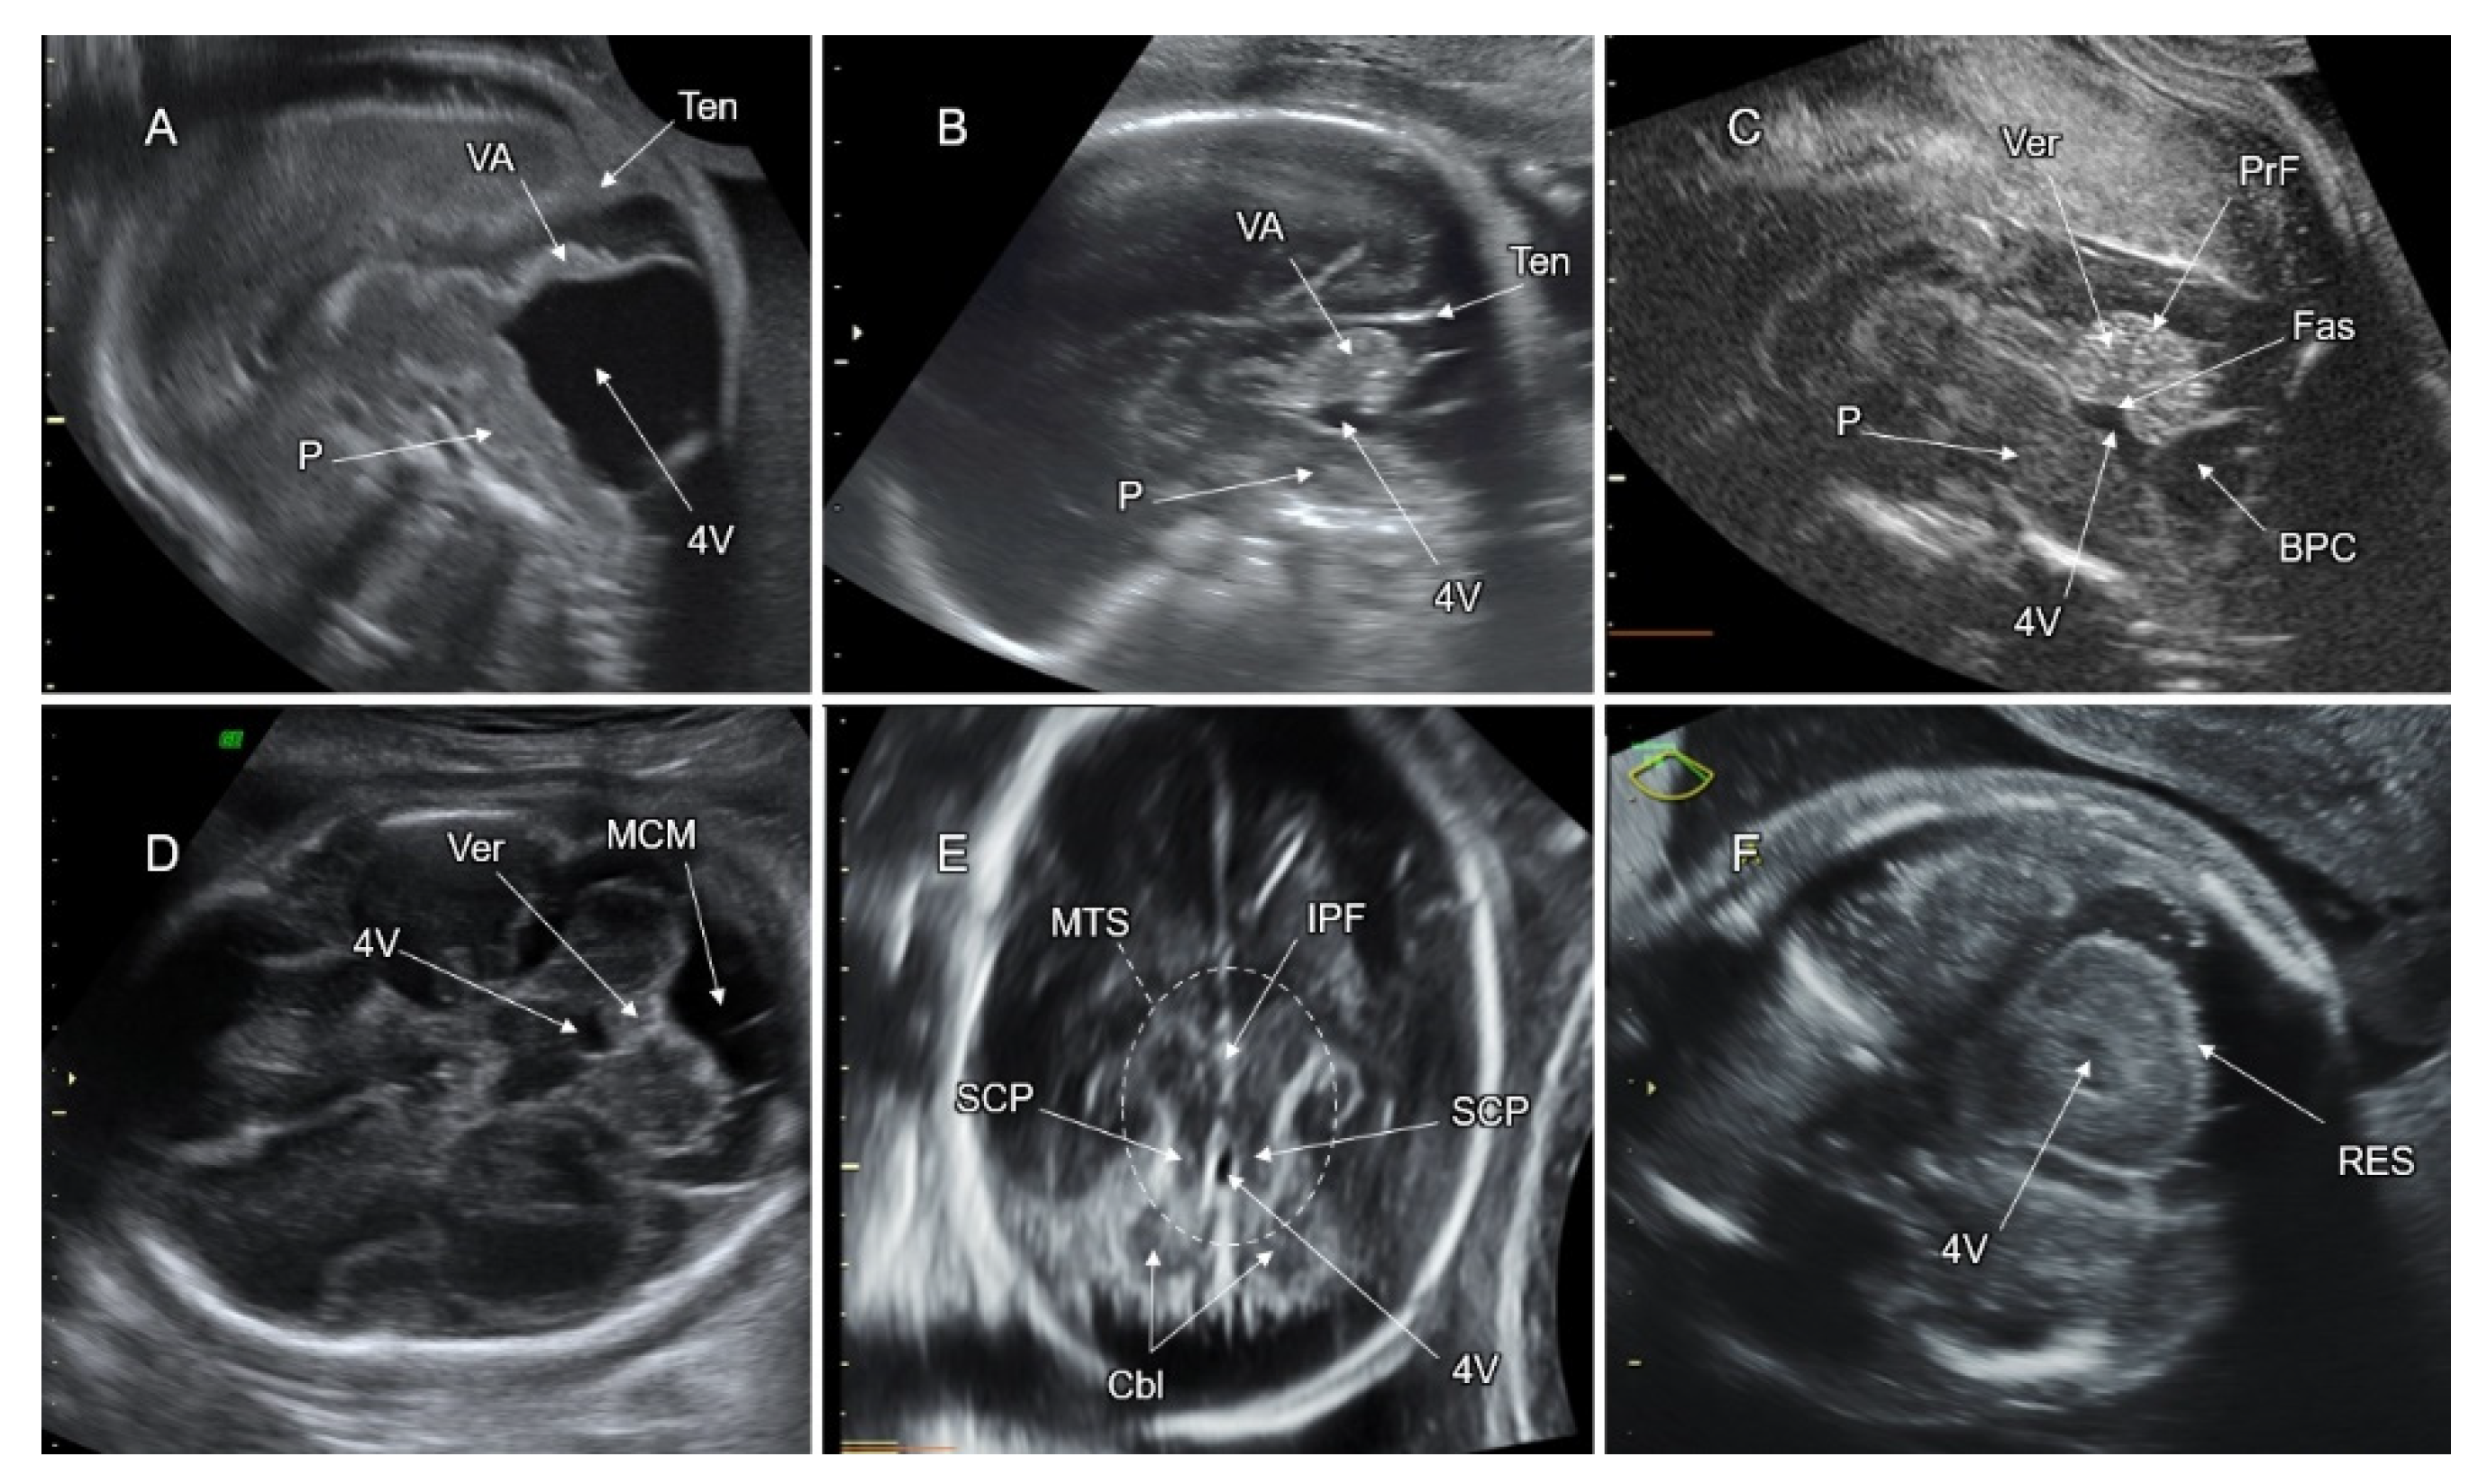

7. Malformations of the Posterior Fossa

7.2. Vermian Agenesis (VA), Hypoplasia (VH), and Dysgenesis (VD)

7.3. Blake’s Pouch Cyst (BPC)

7.4. Mega Cisterna Magna (MCM)

7.5. Joubert Syndrome (JS) and JS-Related Disorders

7.6. Rhombencephalosynapsis (RES)